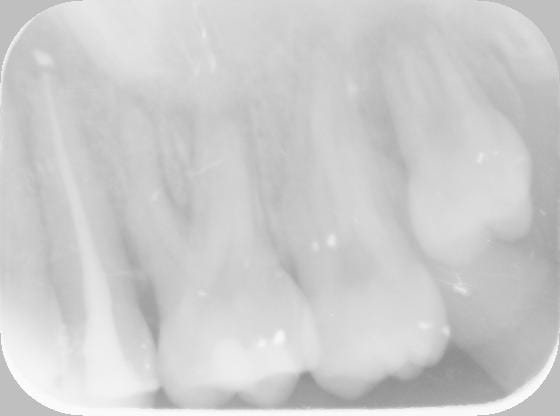

à l'exament clinique il y avait une gingivite et des caries dans ce secteur. après réalisation des soins tjs pareil avec en plus une douleur précise sur la 25: percussion douloureuse, radio ras, test vitalité negatif. le collègue a pensé à une mortification sous composite, il fait un test au fraisage negatif et endo sans anesthésie. mise sous antibio.

elle vient en urgence un samedi avec un tableau assez etrange: 24 25 26 27 extremement mobiles, avec un aspect d'abces en vest et en palatin, fortes douleurs mais à la radio il n'y avait pas de pertes osseuses mais on avait l'impression que le sinus gauche etait un peu radio opaque. etant donné qu'il n'y avait pas d'ortho de faite ni par mon collègue ni par l'orl et qu'il etait impossible de toucher la patiente (à ce moment là on pensait à un abcès aggravé par l'arret des ab et la prescription de solupred) on a adressé la patiente au service de stomato, de plus le fait que la sinusite soit unilatérale et qu'elle soit résistante aux antibiotiques ce n'etait pas très rassurant bien que on ne soupçonnait pas un tel diagnostic.

à postériori ça parait evident comme signes: sinusites unilatérale resistante au antibiotiques sans problèmes dentaires evidents... mais sur le moment on ne pense pas à ça chez une patiente de 17ans. par contre c'est dommage qu'il n'y ait pas eu d'ortho de faite auparavant...

la panoramique qui n'a pas été faite nous aurait peut-être montré que le sinus etait plein, on aurait pu voir si les apex étaient proches du sinus, si le sinus est plein et que la cause dentaire peut etre ecartée==> faut adresser à ORL ou STOMATO, ça aurait été plus rapide sans pour autant y changer quoi que ce soit. je ne sais pas à quel stade est le cancer mais cela aurait pu montrer que l'image radio opaque deborde du sinus... etc etc je me disais seulement que c'etait un cas où la panoramique aurait été utile, dommage qu'elle n'ait pas été demandé auparavant